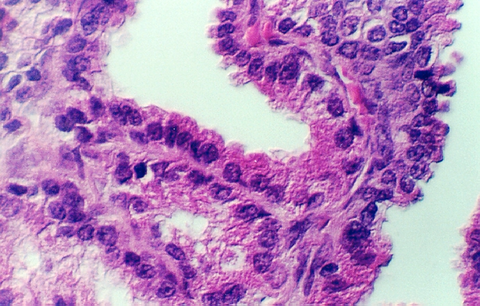

The lumen of this gland is thrown into many folds that appear to branch. This creates a labyrinth of channels, tubes, and pockets into which the secretory product flows. The epithelium shown in the photos below may be simple columnar with patches of pseudostratified epithelium. The appearance of the epithelium is variable and dependent on age and the level of androgen production. One can see some lipochrome pigment in the epithelium, which is present in elderly males. Look at the wall of the gland and again, there are numerous bundles of smooth muscle.

What does the seminal vesicle contribute to the semen?